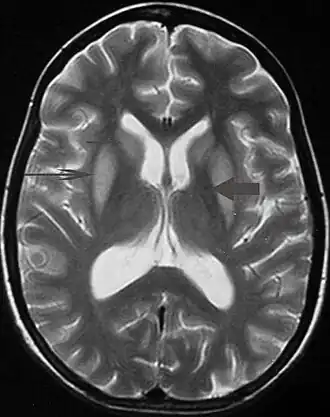

Ressonância de um paciente com parkinsonismo severo.

Tremor pode ser um sintoma associado a distúrbios nas partes do cérebro que controlam os músculos de todo o corpo ou em áreas específicas, tais como as mãos. Dentre os problemas neurológicos que podem produzir tremor incluem-se: hipertireoidismo, esclerose múltipla, acidente vascular cerebral, traumatismo craniano, doença renal crônica, doenças neurodegenerativas que danificam ou destroem partes do tronco cerebral ou o do cerebelo, sendo a doença de Parkinson o mais frequentemente associados com tremor. Transtornos neurológicos que causem tremor são chamados de parkinsonismo.